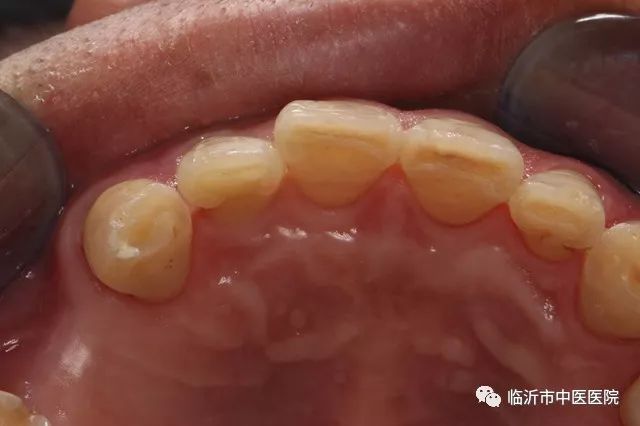

徐宝军主任说,前牙外伤折断,可由于受力方向,部位及力量的大小不同,其折断的部位,情势不一样,修复方法也不一样。当病人就诊时,医生首先要检查患牙折断的部位,牙髓是否暴露。如果门牙折断一小部分,未伤及牙髓,X线显示根端完好,无折断或脱位,牙齿基本稳固,可用粘接方法直接再接断牙。在粘接之前,先清洁牙齿断面,并进行酸蚀处理,用水冲洗,干燥,于断面涂粘接剂,对准位置加压粘接,用光照固化。为加强粘接牢固性,往往在断面采用金属丝支架加固。

如果门牙牙折断面积较大,牙髓暴露,但根部完好,牙齿不松动,应首先在局麻下进行牙髓治疗即根管治疗,治疗后,在牙断面打两根螺纹钉,然后将断端复位,再取下备用。断面经粘接前的处理,涂粘接剂,用树脂充填牙髓腔,将断面对准粘接,光照固化。亦可在断面粘接后,将牙表面磨去一薄层,用贴面材料覆盖,修整外形,磨光,这时患牙的外形颜色与邻牙协调。

王振主任强调,遇到门牙牙冠于牙龈部位折断时,断冠完整无裂纹,根部稳无折断,可行接冠术。首先对断面进行清理,然后常规进行根管治疗,充填应密合。如断面在牙龈下,先将覆盖的牙龈组织切除,充分暴露断面。上述治疗完成后,再行接冠。选用成品或自制铸造桩钉,插入制备后的根管内,将断端调磨试接,直至复位,再取下备用。将桩钉粘固于根管内,断面进行粘接术前常规处理后于断面涂粘接剂及树脂材料,把断冠按位置复位,去除多余材料,光照固化。粘接完成后,适当调改咬颌,减轻患牙颌力。